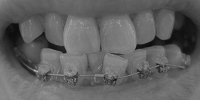

下の歯を奥に引っ込めて行く予定だったのですが、今回全然動かなかったのでまたもや見送りという結果

上下ともワイヤーを太くして、もう少し凸凹をきれいに揃えることに。

そんなわけで、ここんとこ変化がなくて寂しいので、この7ヶ月の変化が分かるように写真を並べて自分を励ますことにします~

なるほど、綺麗に揃ってますね! デーモンシステムって凄いです。

ねね、全然違いますよね!!

正面から見たところなんて、こうやって見ると別人ですよね。

揃うのは、あと数ヶ月でいけると思います~。

問題は抜歯の後を詰めるために、後ろにひっぱっていく作業なのです~。